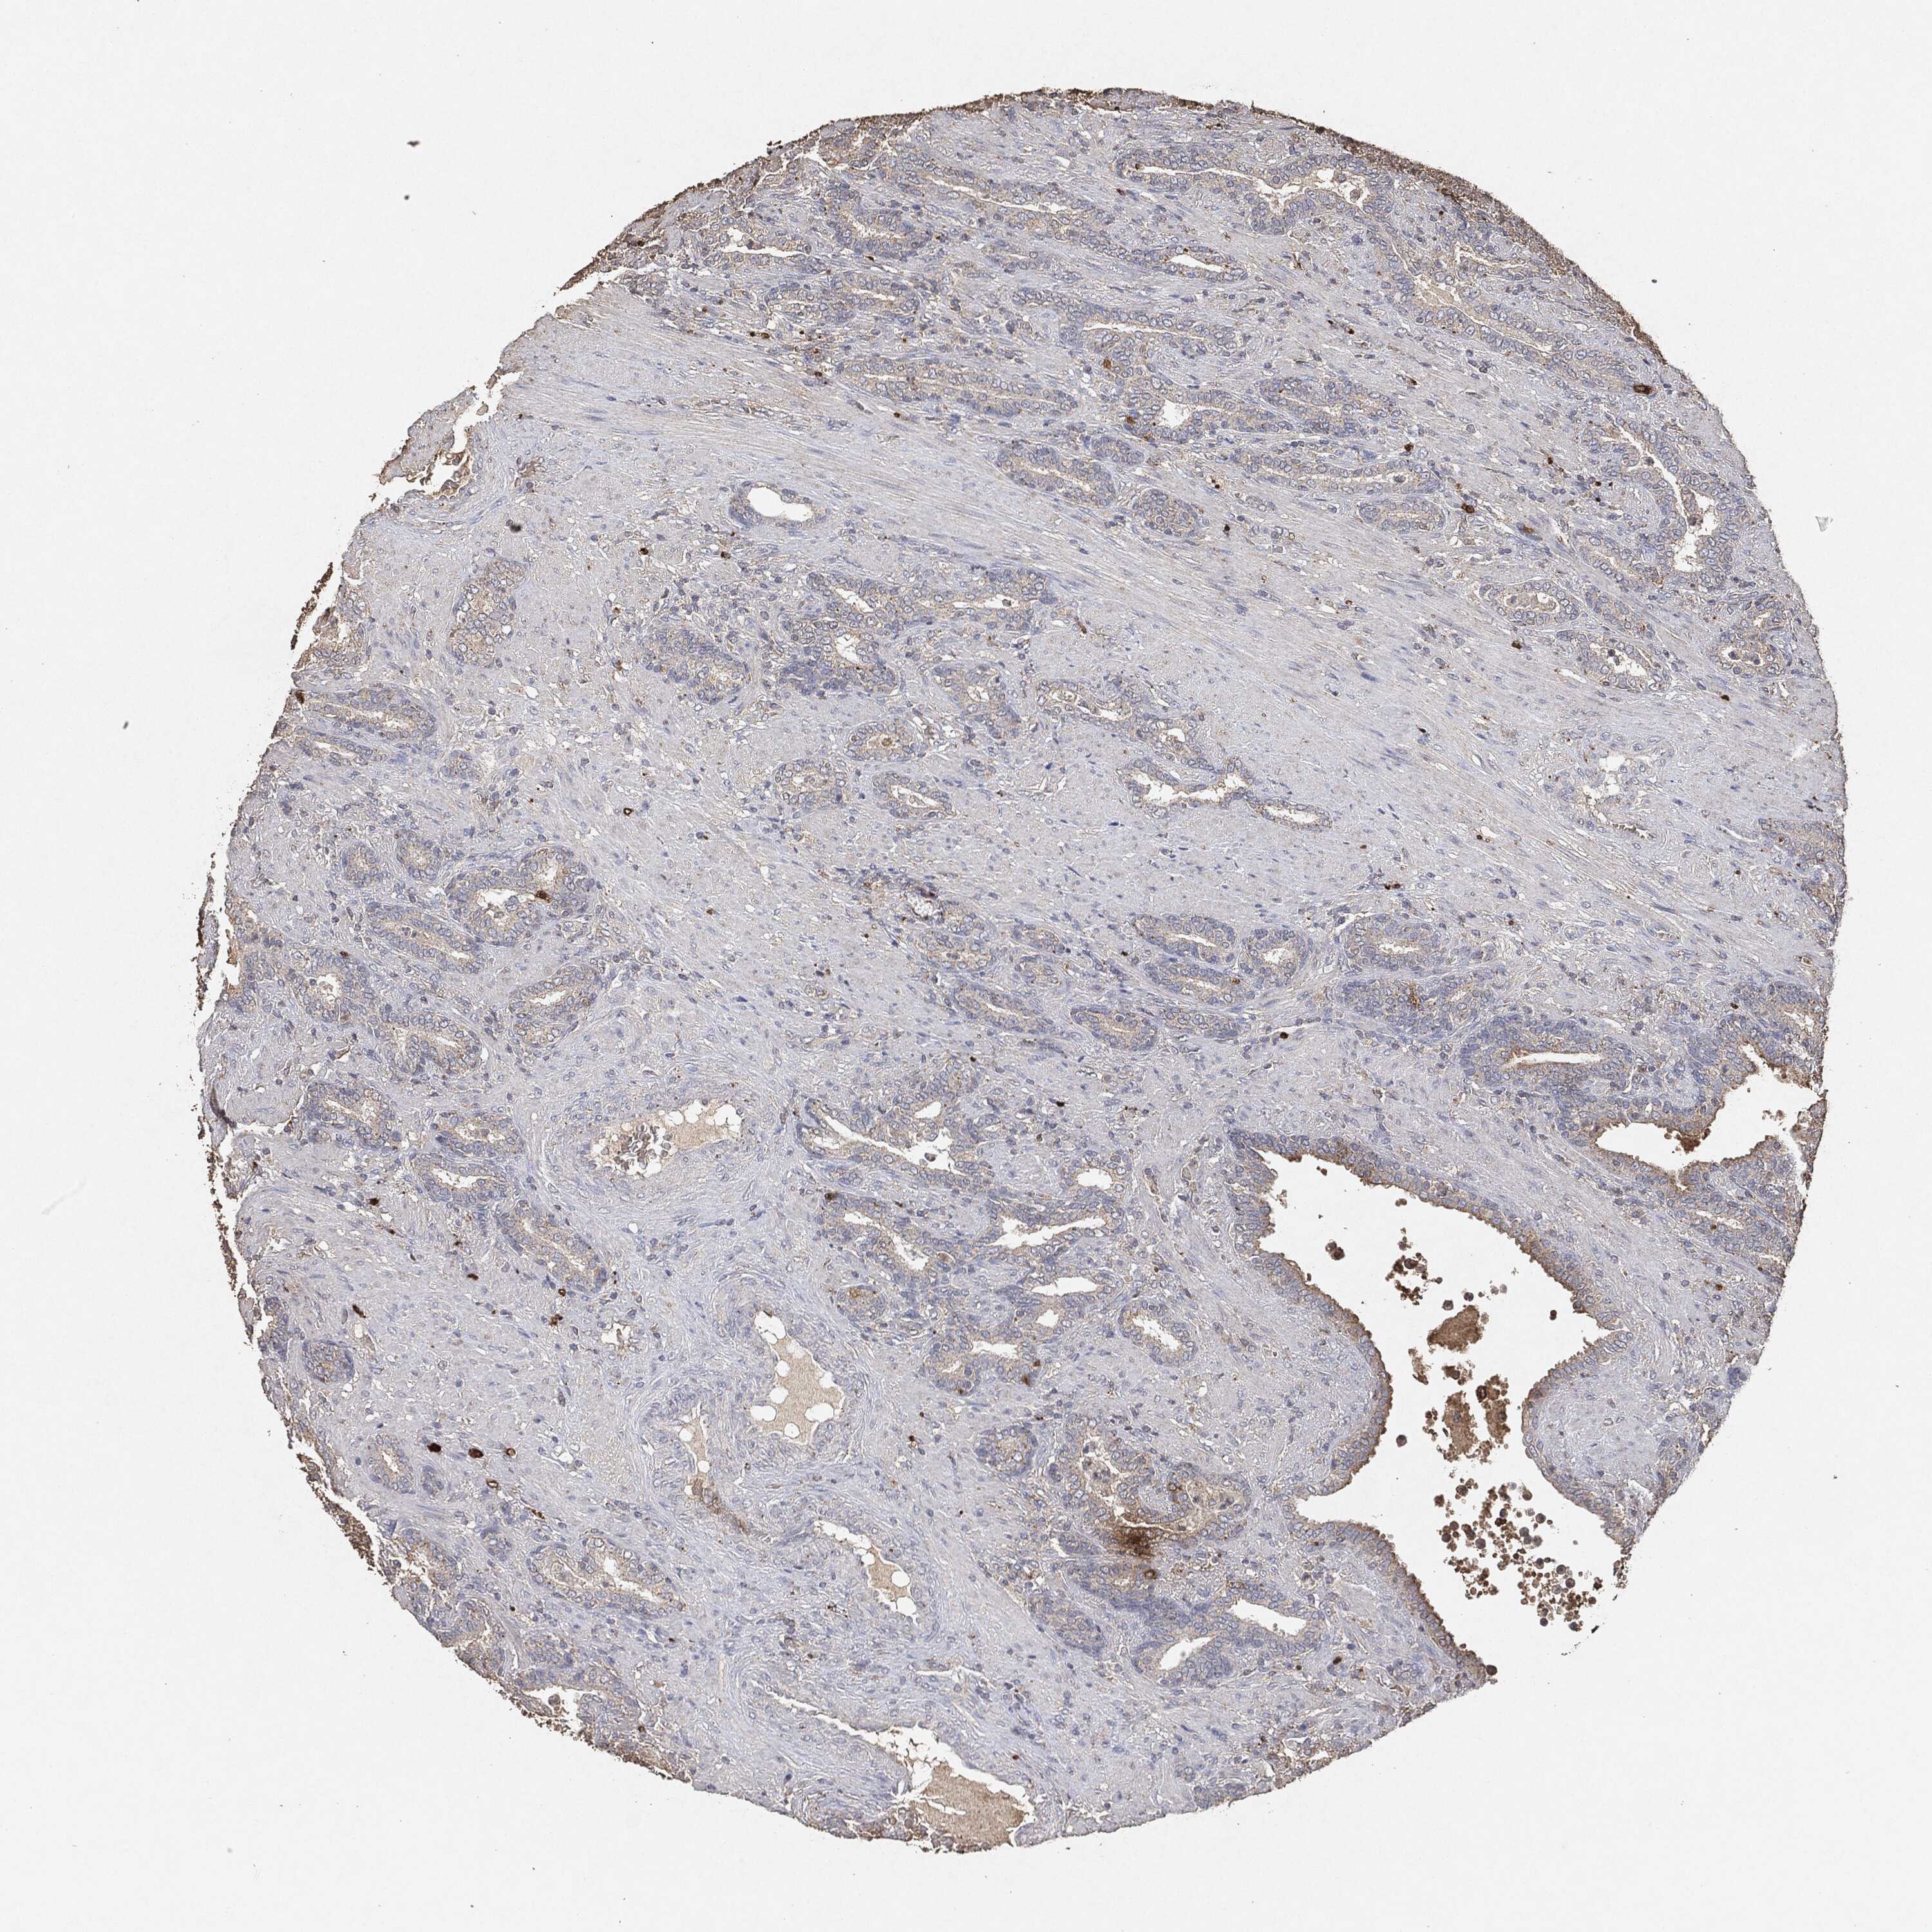

PROSTATE CANCER - Protein expressioni

A mouse-over function shows sample information and annotation data. Click on an image to view it in a full screen mode. Samples can be filtered based on level of antibody staining by selecting one or several of the following categories: high, medium, low and not detected. The assay and annotation is described here.

Note that samples used for immunohistochemistry by the Human Protein Atlas do not correspond to samples in the TCGA dataset.

Antibody stainingi

Antibody staining in the annotated cell types in the current human tissue is reported as not detected, low, medium, or high, based on conventional immunohistochemistry profiling in selected tissues. This score is based on the combination of the staining intensity and fraction of stained cells.

Each image is clickable and will lead to virtual microscopy that enables deeper exploration of all samples and also displays staining intensity scores, fraction scores and subcellular localization as well as patient and tissue information for each sample.

Adenocarcinoma, Medium grade

Adenocarcinoma, Low grade

Adenocarcinoma, High grade

Adenocarcinoma, NOS